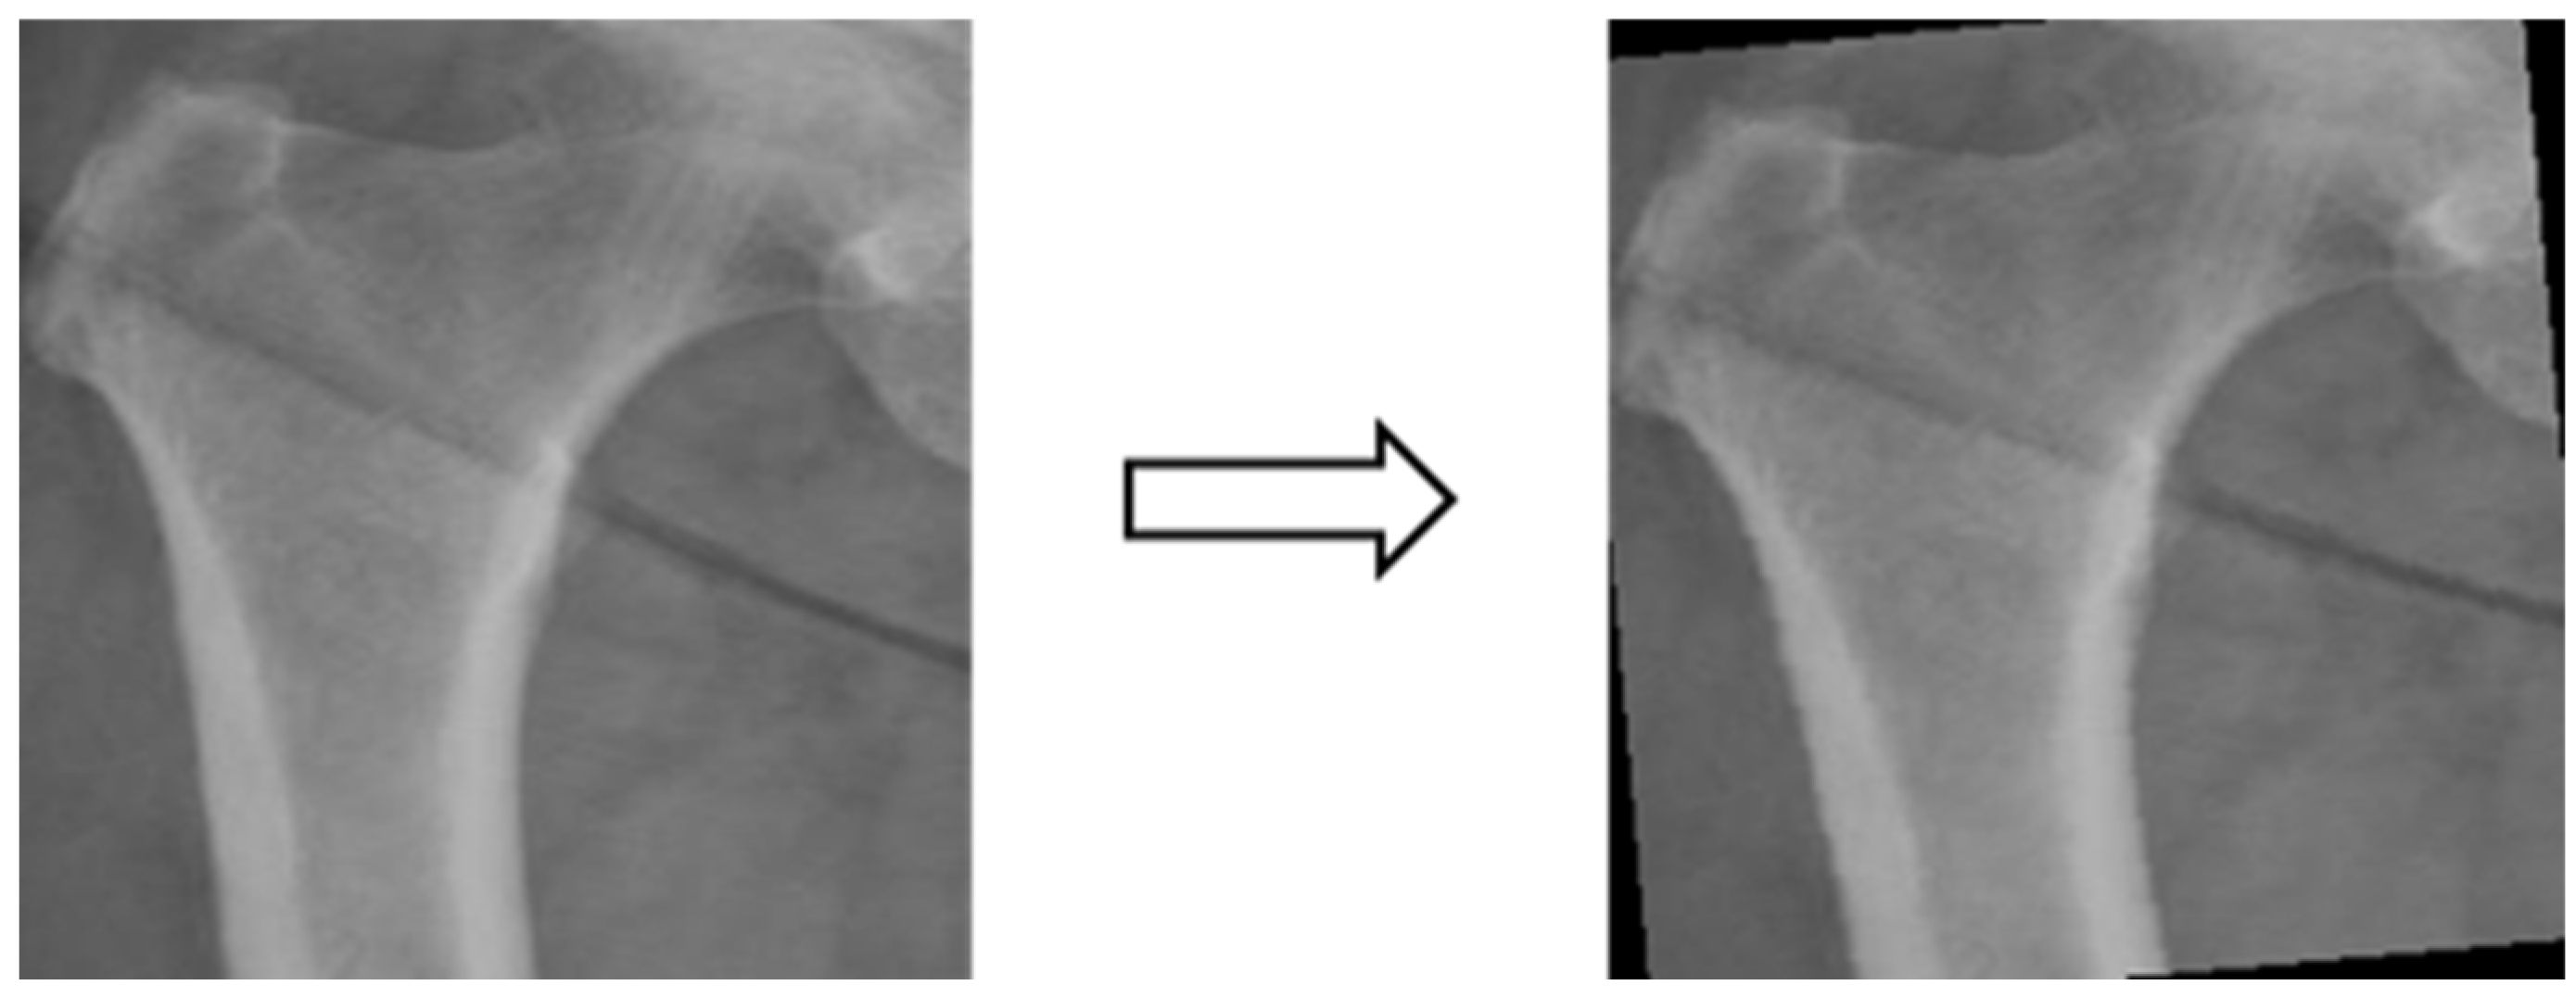

3.3.4. Data Augmentation

In this study, the X-ray image data were insufficient for image classification experiments. Training the model with the original dataset could lead to issues such as model underfitting and poor generalization due to the low complexity of the model and the limited image features. Therefore, the dataset consisting of X-ray images from four different body areas was augmented by applying transformations like rotation (e.g., Figure 5), shifting (e.g., Figure 6), and random scaling (e.g., Figure 7). Importantly, these augmentations were performed without altering the bone contour morphology, background, or color. The purpose of data augmentation was to aid in the training of deep learning models [30]. Additionally, data augmentation serves to address underfitting problems in classification experiments and can potentially enhance experimental accuracy if overfitting issues arise in the future [31]. Table 1 presents a comparison of data volume before and after data augmentation.

Figure 5.

Image rotation.